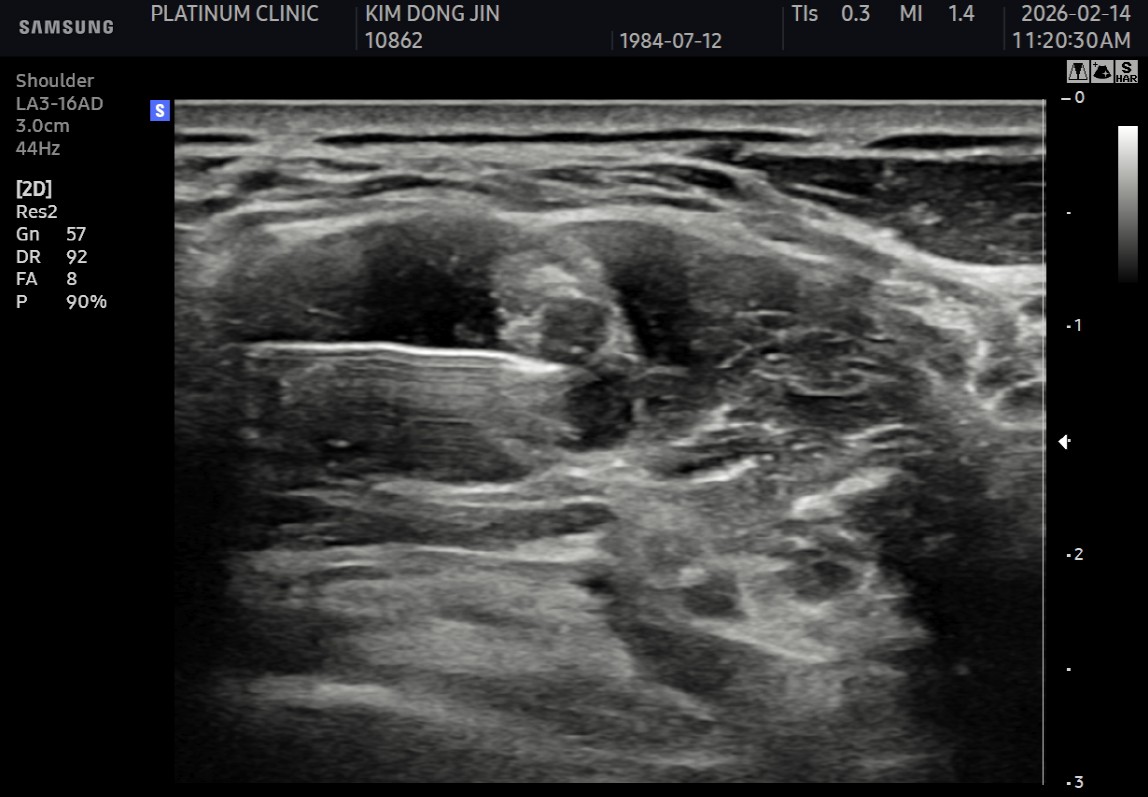

10주 후 초음파:

봉합 부위가 정상 인대처럼 하얗게 재생되어 있었습니다. 골수자극의 효과로 예상보다 빠른 재생이 확인되었습니다.

- ✓관절면측: 봉합 부위 안정적 유지

- ✓점액낭면측: 인대 두께 4.8mm → 6.5mm (1.7mm 증가)